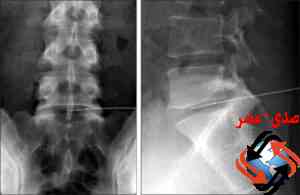

تم لأول مرة فى مستشفيات دمياط .. اجراء عملية تردد حرارى كى لفقرات للمفاصل الفقرية العمود الفقرى وكى نواة الغضروف بالتردد الحرارى للغضروف القطنى تحت التصوير الفلورسكوبى .. و ذلك للمرة الاولى بمحافظة دمياط بمستشفى دمياط العام لسيدة تعانى من الام والتهاب بمفاصل فقرات العمود الفقرى بعد اجراء التحاليل والفحوصات والاشعات اللازمة للحالة